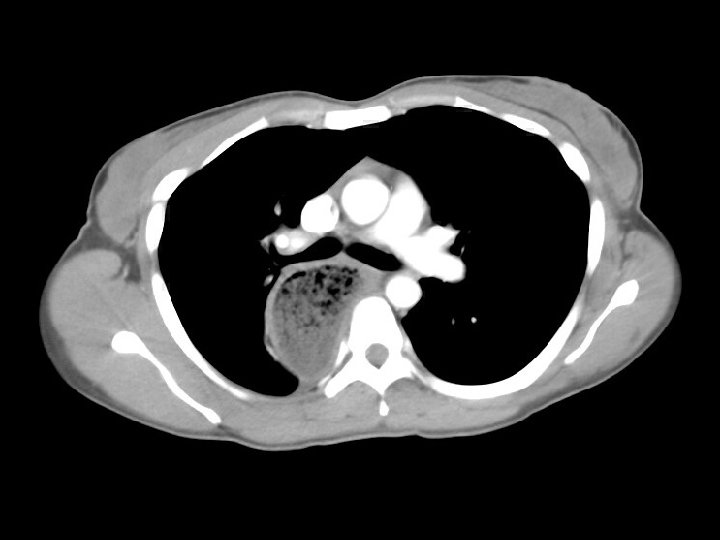

Achalasia • Findings: – Dilated and debrisfilled esophagus • ddx: – Pseudoachalasia • Obstructing tumor • Benign or malignant stricture • Chaga’s disease – Posterior mediastinal abscess